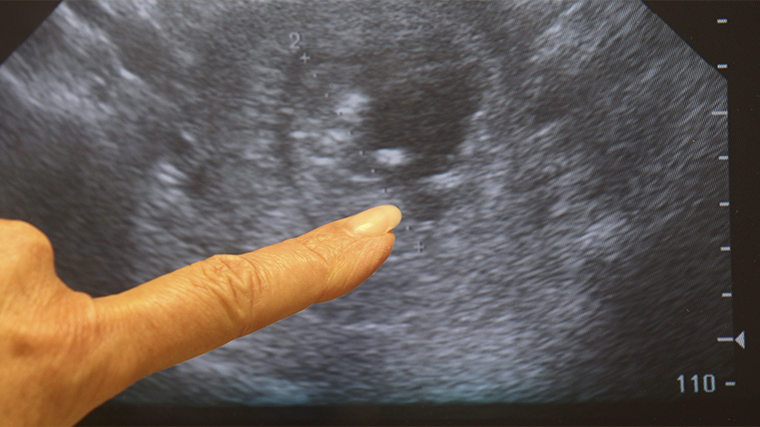

«Золотым стандартом» является анализ на хорионический гонадотропин человека (ХГЧ). Он может быть в виде обычного аптечного теста, либо вы также можете сдать анализ крови на ХГЧ. И также к достоверным методам обследования является УЗИ малого таза, подчеркивает эксперт.

УЗИ же не только подтверждает наличие плодного яйца, но и позволяет оценить его расположение, исключая внематочную беременность.

«Все эти признаки и методы, они могут лишь вам дать пищу для ума, для размышлений, но они не заменят точной диагностики. А это либо мочевой тест на ХГЧ, аптечный, обычный, можно сдать кровь на ХГЧ, а также УЗИ малого таза», — резюмирует акушер.

Ранняя постановка на учет позволяет своевременно выявить возможные риски, получить рекомендации по питанию и образу жизни, а также провести первое УЗИ, которое подтвердит, что плодное яйцо находится в матке и развивается правильно.

Важно помнить, что даже если тест оказался положительным, а УЗИ пока не проводилось, врач уже на раннем сроке может оценить состояние слизистой матки, исключить внематочную беременность и дать рекомендации по дальнейшему ведению беременности.